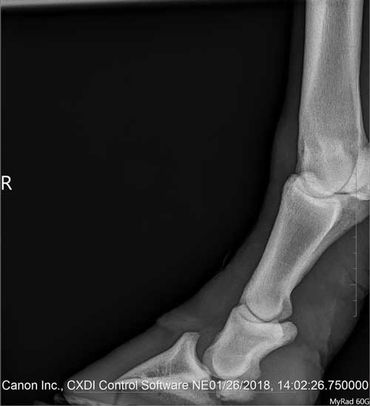

Zoe started going a bit lame in her leg so we had the vet out on June 24, 2020.

We decided to get her Coffin- and Pastern Joint injected again.

The vet bill for the injections done with a radiographic guidance and farm call was $ 375.